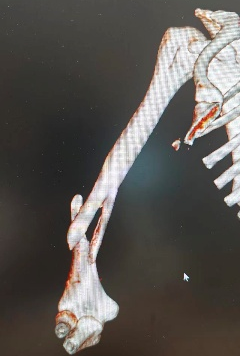

10月1日,李女士(化名)因车祸致右上肢骨折,13:30入院,黄磊医师团队完善各项检查后于18:00实行右肱骨骨折切开复位内固定术, 20:00安返病房。